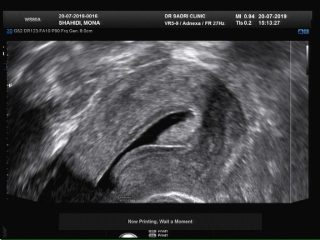

در تصویر زیر نمونه ای از خونریزی غیر طبیعی رحمی در فردی که در حول زمان یائسگی می باشد مشاهده می فرمایید:

عکس مربوط به سونو هیسترو است و در قسمت بالای کاویته رحمی تصویر یک پولیپ با پدیکل عروقی آن که از لایه قدامی اندومتر منشا گرفته رویت میشود: